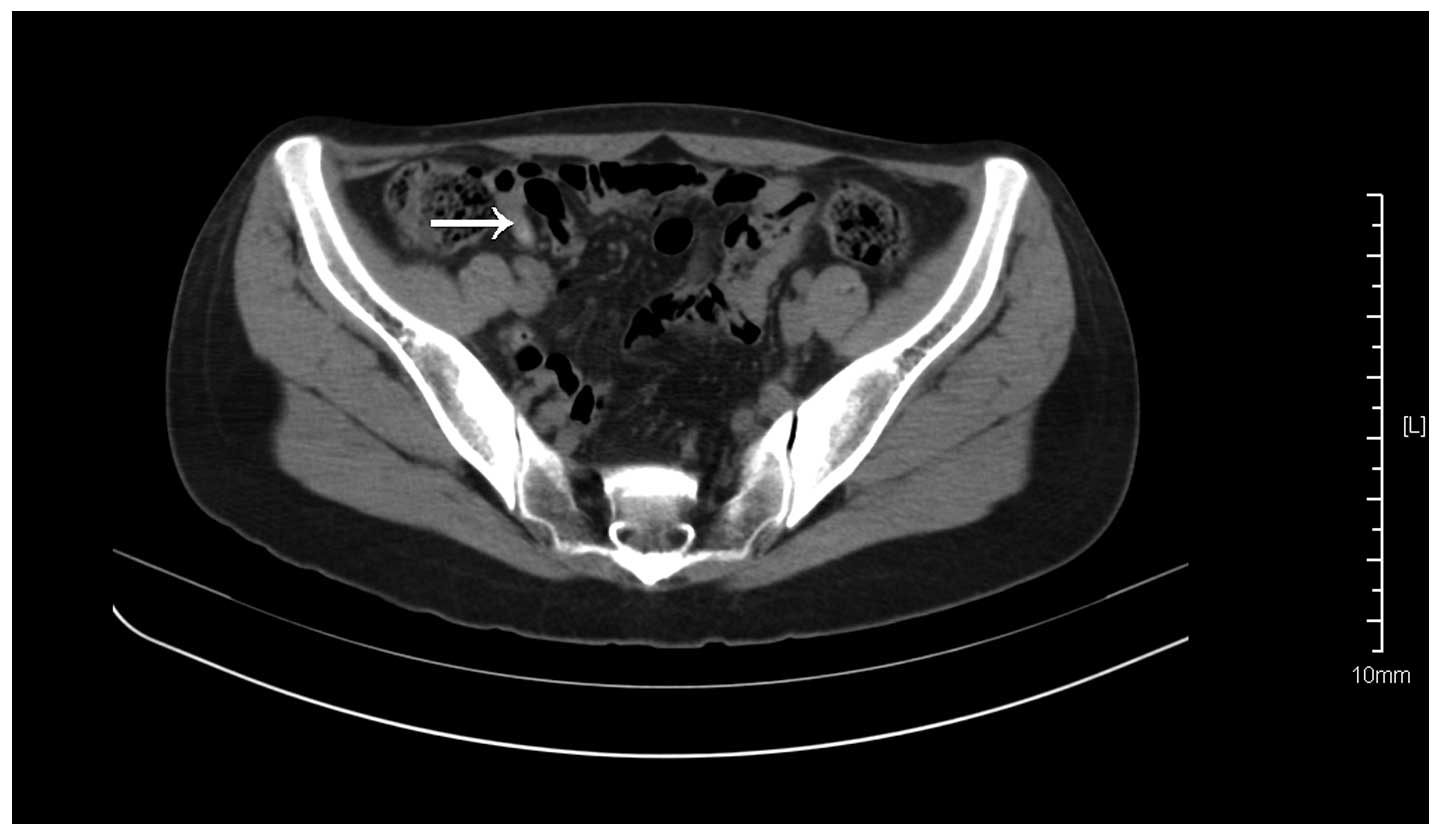

The patient reported a three-year history of recurrent dull right lower abdominal pain that had not been considered serious enough to obtain medical assistance. Three days prior to admittance, the aforementioned symptoms became aggravated and the patient presented to the Taicang Hospital Affiliated to Soochow University. Physical examination revealed a body temperature of 36.5°C, blood pressure of 111/78 mmHg and a pulse rate of 95 beats/min. During assessment, the patient experienced light direct tenderness, but no rebound tenderness, in the right lower abdomen. No palpable masses were observed in the abdomen. Laboratory tests were performed, yielding the following results: White blood cell count, 4.4×109 cells/l (normal range, 4–10×109 cells/l); neutrophil proportion, 46.8% (normal range, 45–80%); hemoglobin level, 130 g/l (normal range, 110–150 g/l); platelet count, 177×109 platelets/l (normal range, 100–300×109 platelets/l). In addition, abdominal computed tomography revealed appendiceal inflammation, while the tumor was too small to identify (Fig. 1). The patient possessed no previous medical history and no family medical history of appendicitis.

Figure 1.

Computed tomography scan revealing the appendix, with the tumor being too small to identify, as indicated by the arrow.